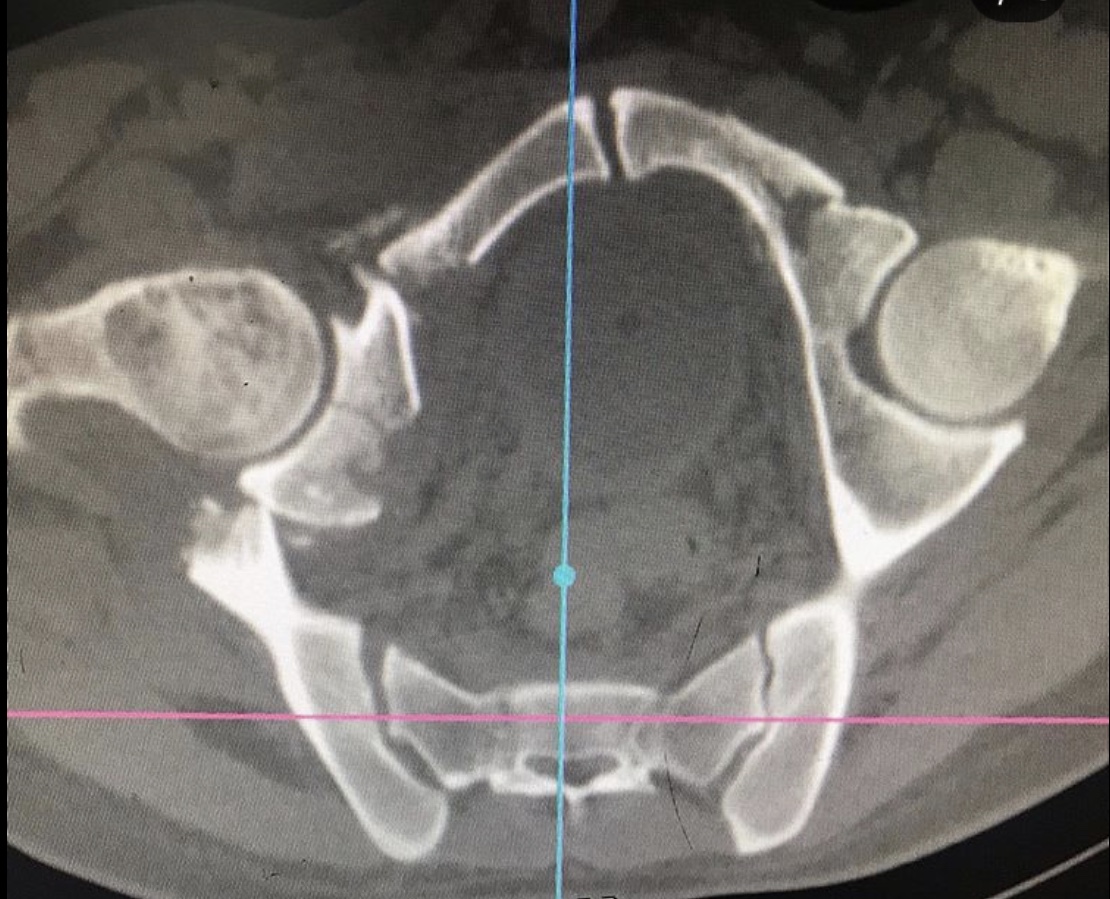

Перелом таза – тяжелейшая травма костей скелета, уступающая по опасности только травмам позвоночника и черепа. Она отличается особой опасностью, так как ее сопровождают обильная потеря крови и шока. Пострадавшему требуется экстренная врачебная помощь, иначе высок риск гибели. Даже при срочном врачебном вмешательстве не всегда удается спасти пострадавшего, который может погибнуть от кровопотери или осложнений болевого травматического шока.

Была выполнена открытая репозиция, остеосинтез пластинами.